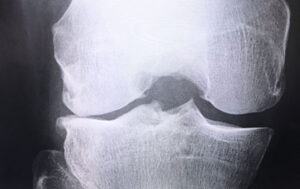

・骨軟化症(イタイイタイ病)